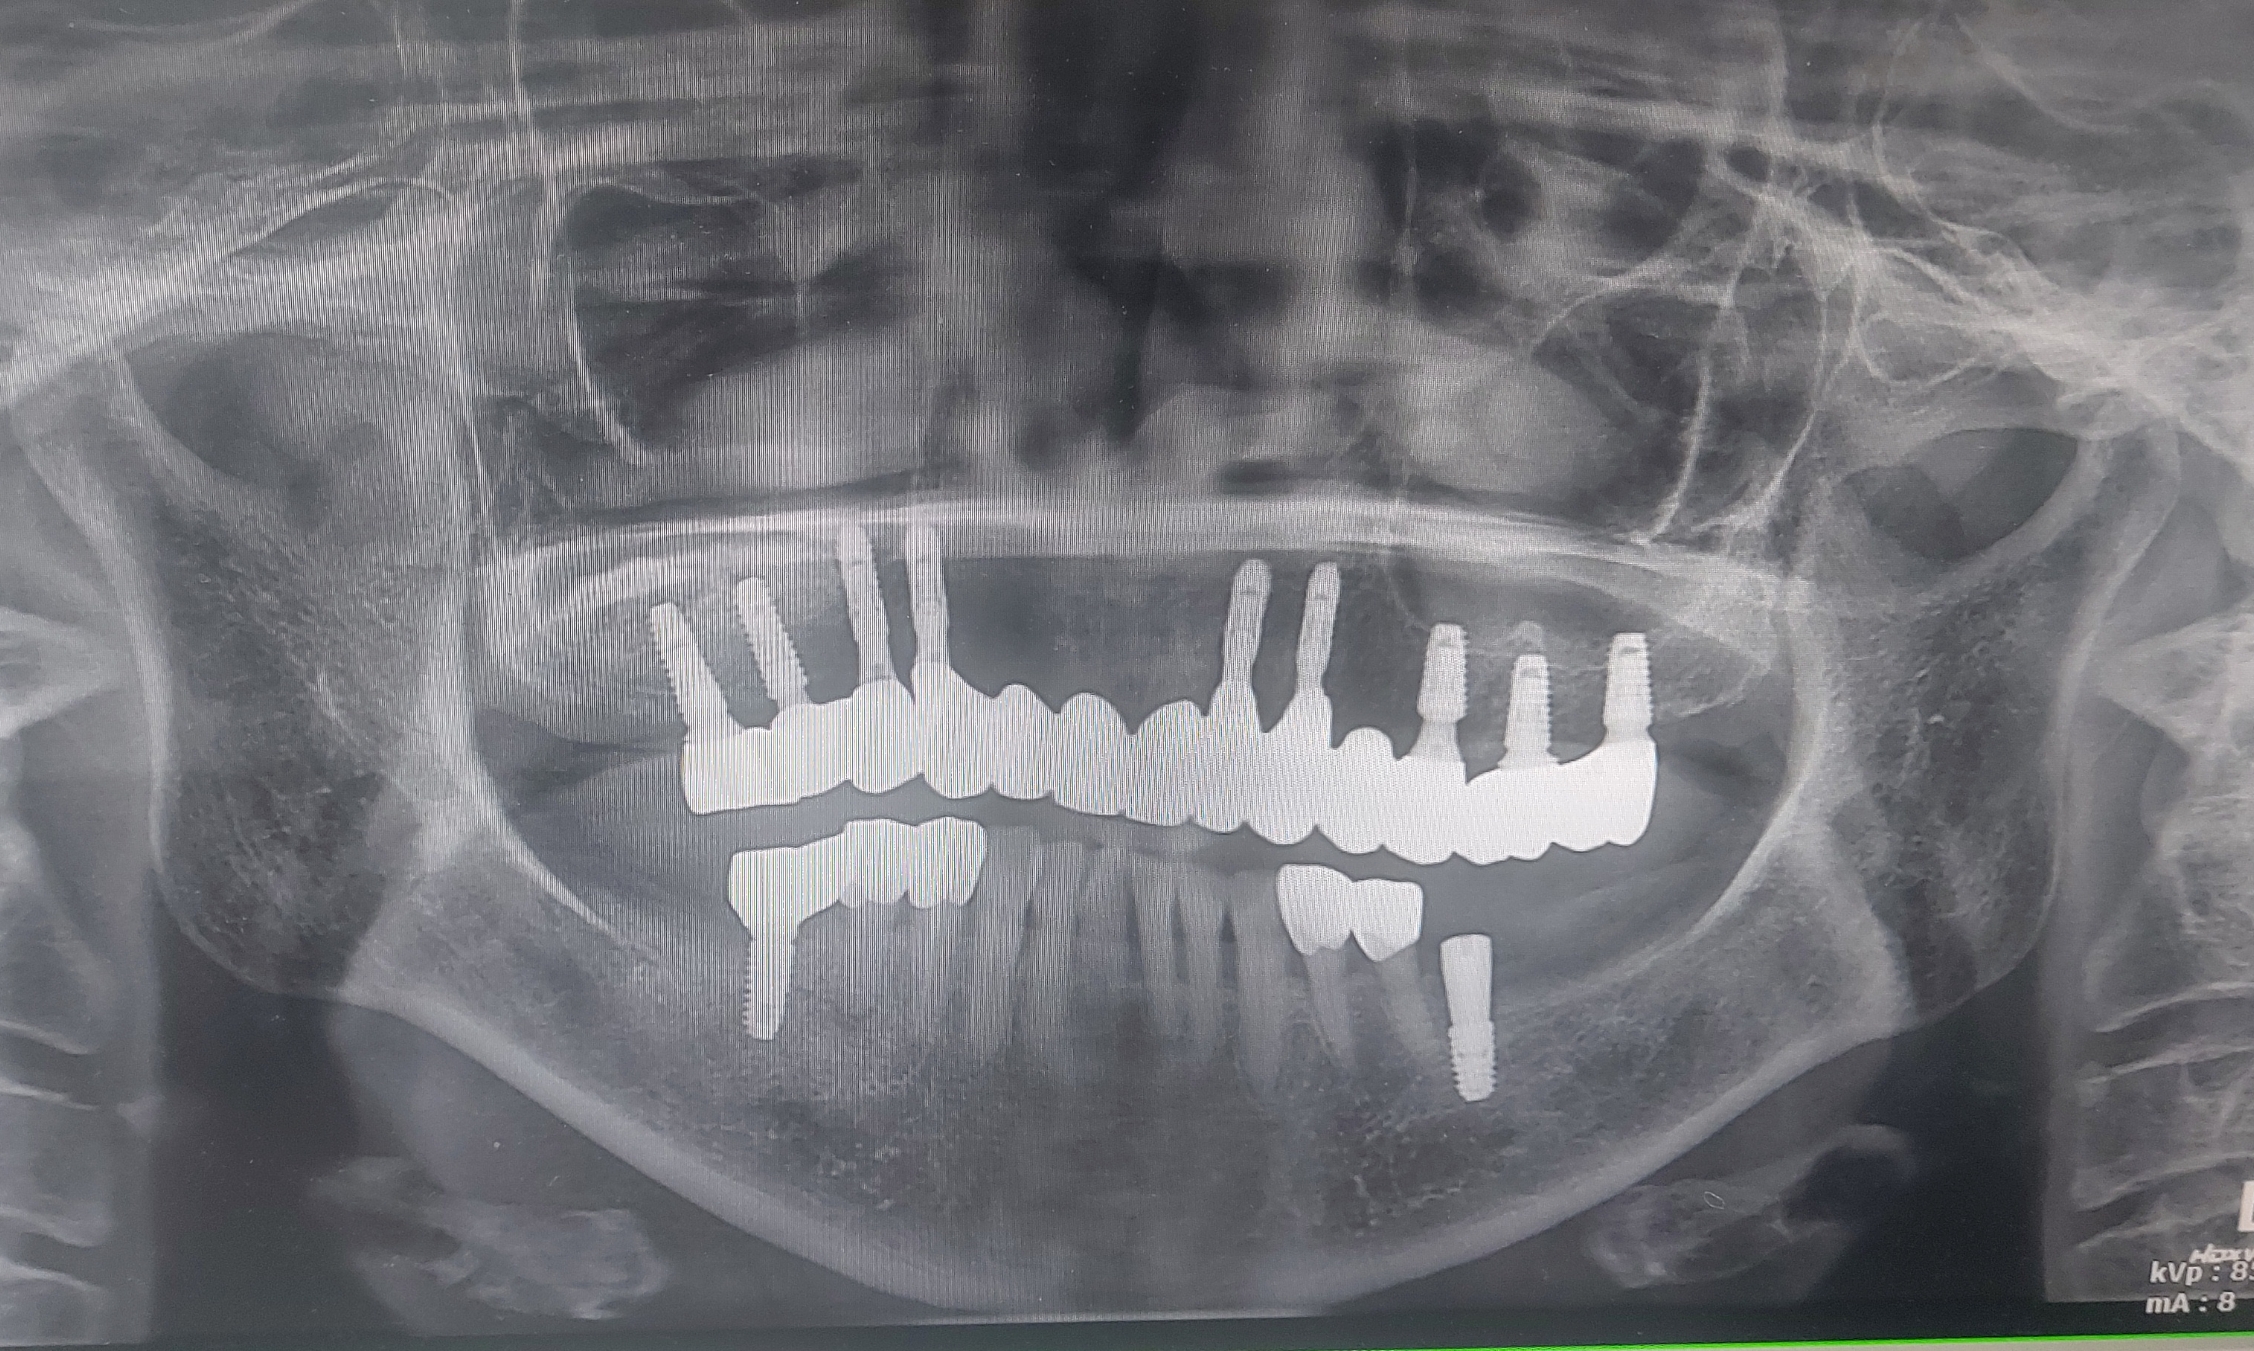

수술후 약 8개월 뒤의 사진입니다.

오른쪽 골이식부위가 수술 초기와 비교해서 많이 골화되어있음이 관찰됩니다.

사용한 이식재료는 이종골인 Inteross 제품을 사용하였습니다.